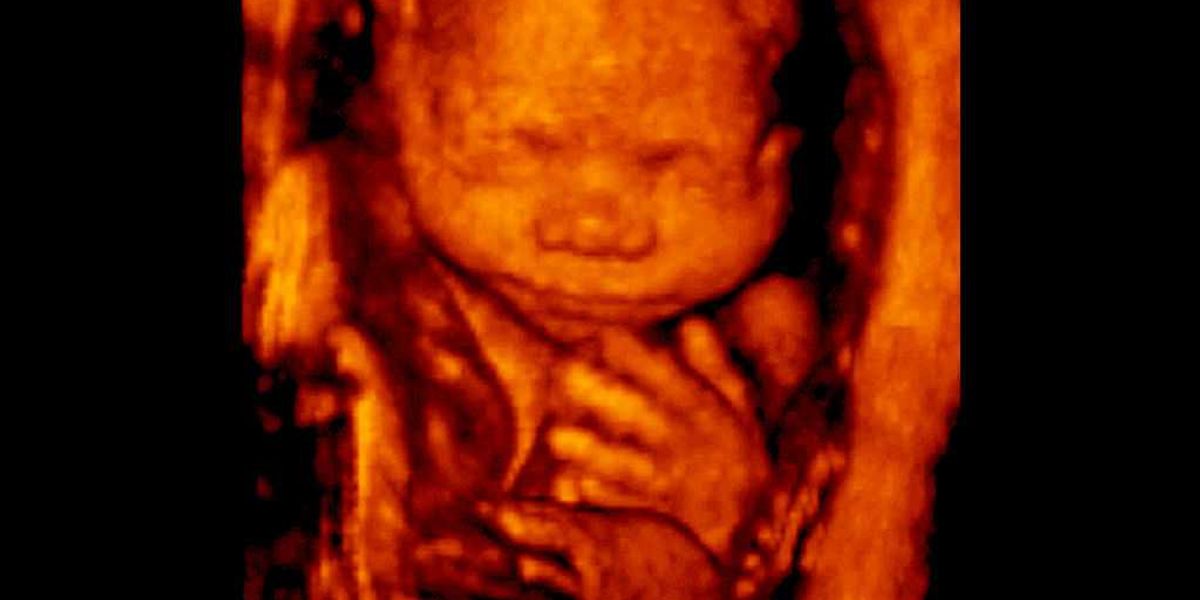

The law 'protects unborn children throughout gestation from abortion, except to prevent the death of the mother as well as other exceptions.'